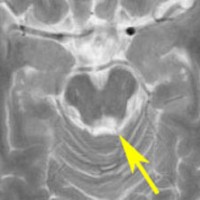

左はT1強調画像,右はFLAIR画像です。中脳視蓋が腫れて腫瘍がにじむように広がっているのがわかります。この腫瘍本体は15歳の時から21歳の時まで大きくなっていないので,中脳視蓋グリオーマ tectal gliomaの診断です。

T1強調ガドリニウム増強画像です。15歳の時は腫瘍の半分以上が強くガドリニウム増強されていましたが,この21歳の時の画像では,中心部やや右寄りに増強像が認められるだけです。この性質は,腫瘍が毛様細胞性星細胞腫であることを示しています。

左はT2強調画像,右はFLAIR画像です。中脳視蓋 tectum の中でも上丘が腫瘍化していることが解りますし,松果体は正常の大きさで腫瘍の上に乗っていますから,松果体腫瘍ではないことが解ります。上髄帆にも浸潤しています。